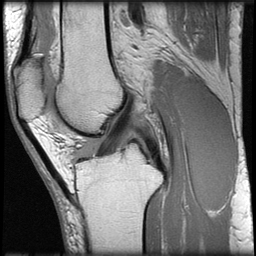

Анатомия и слои коленного сустава: подробное руководство